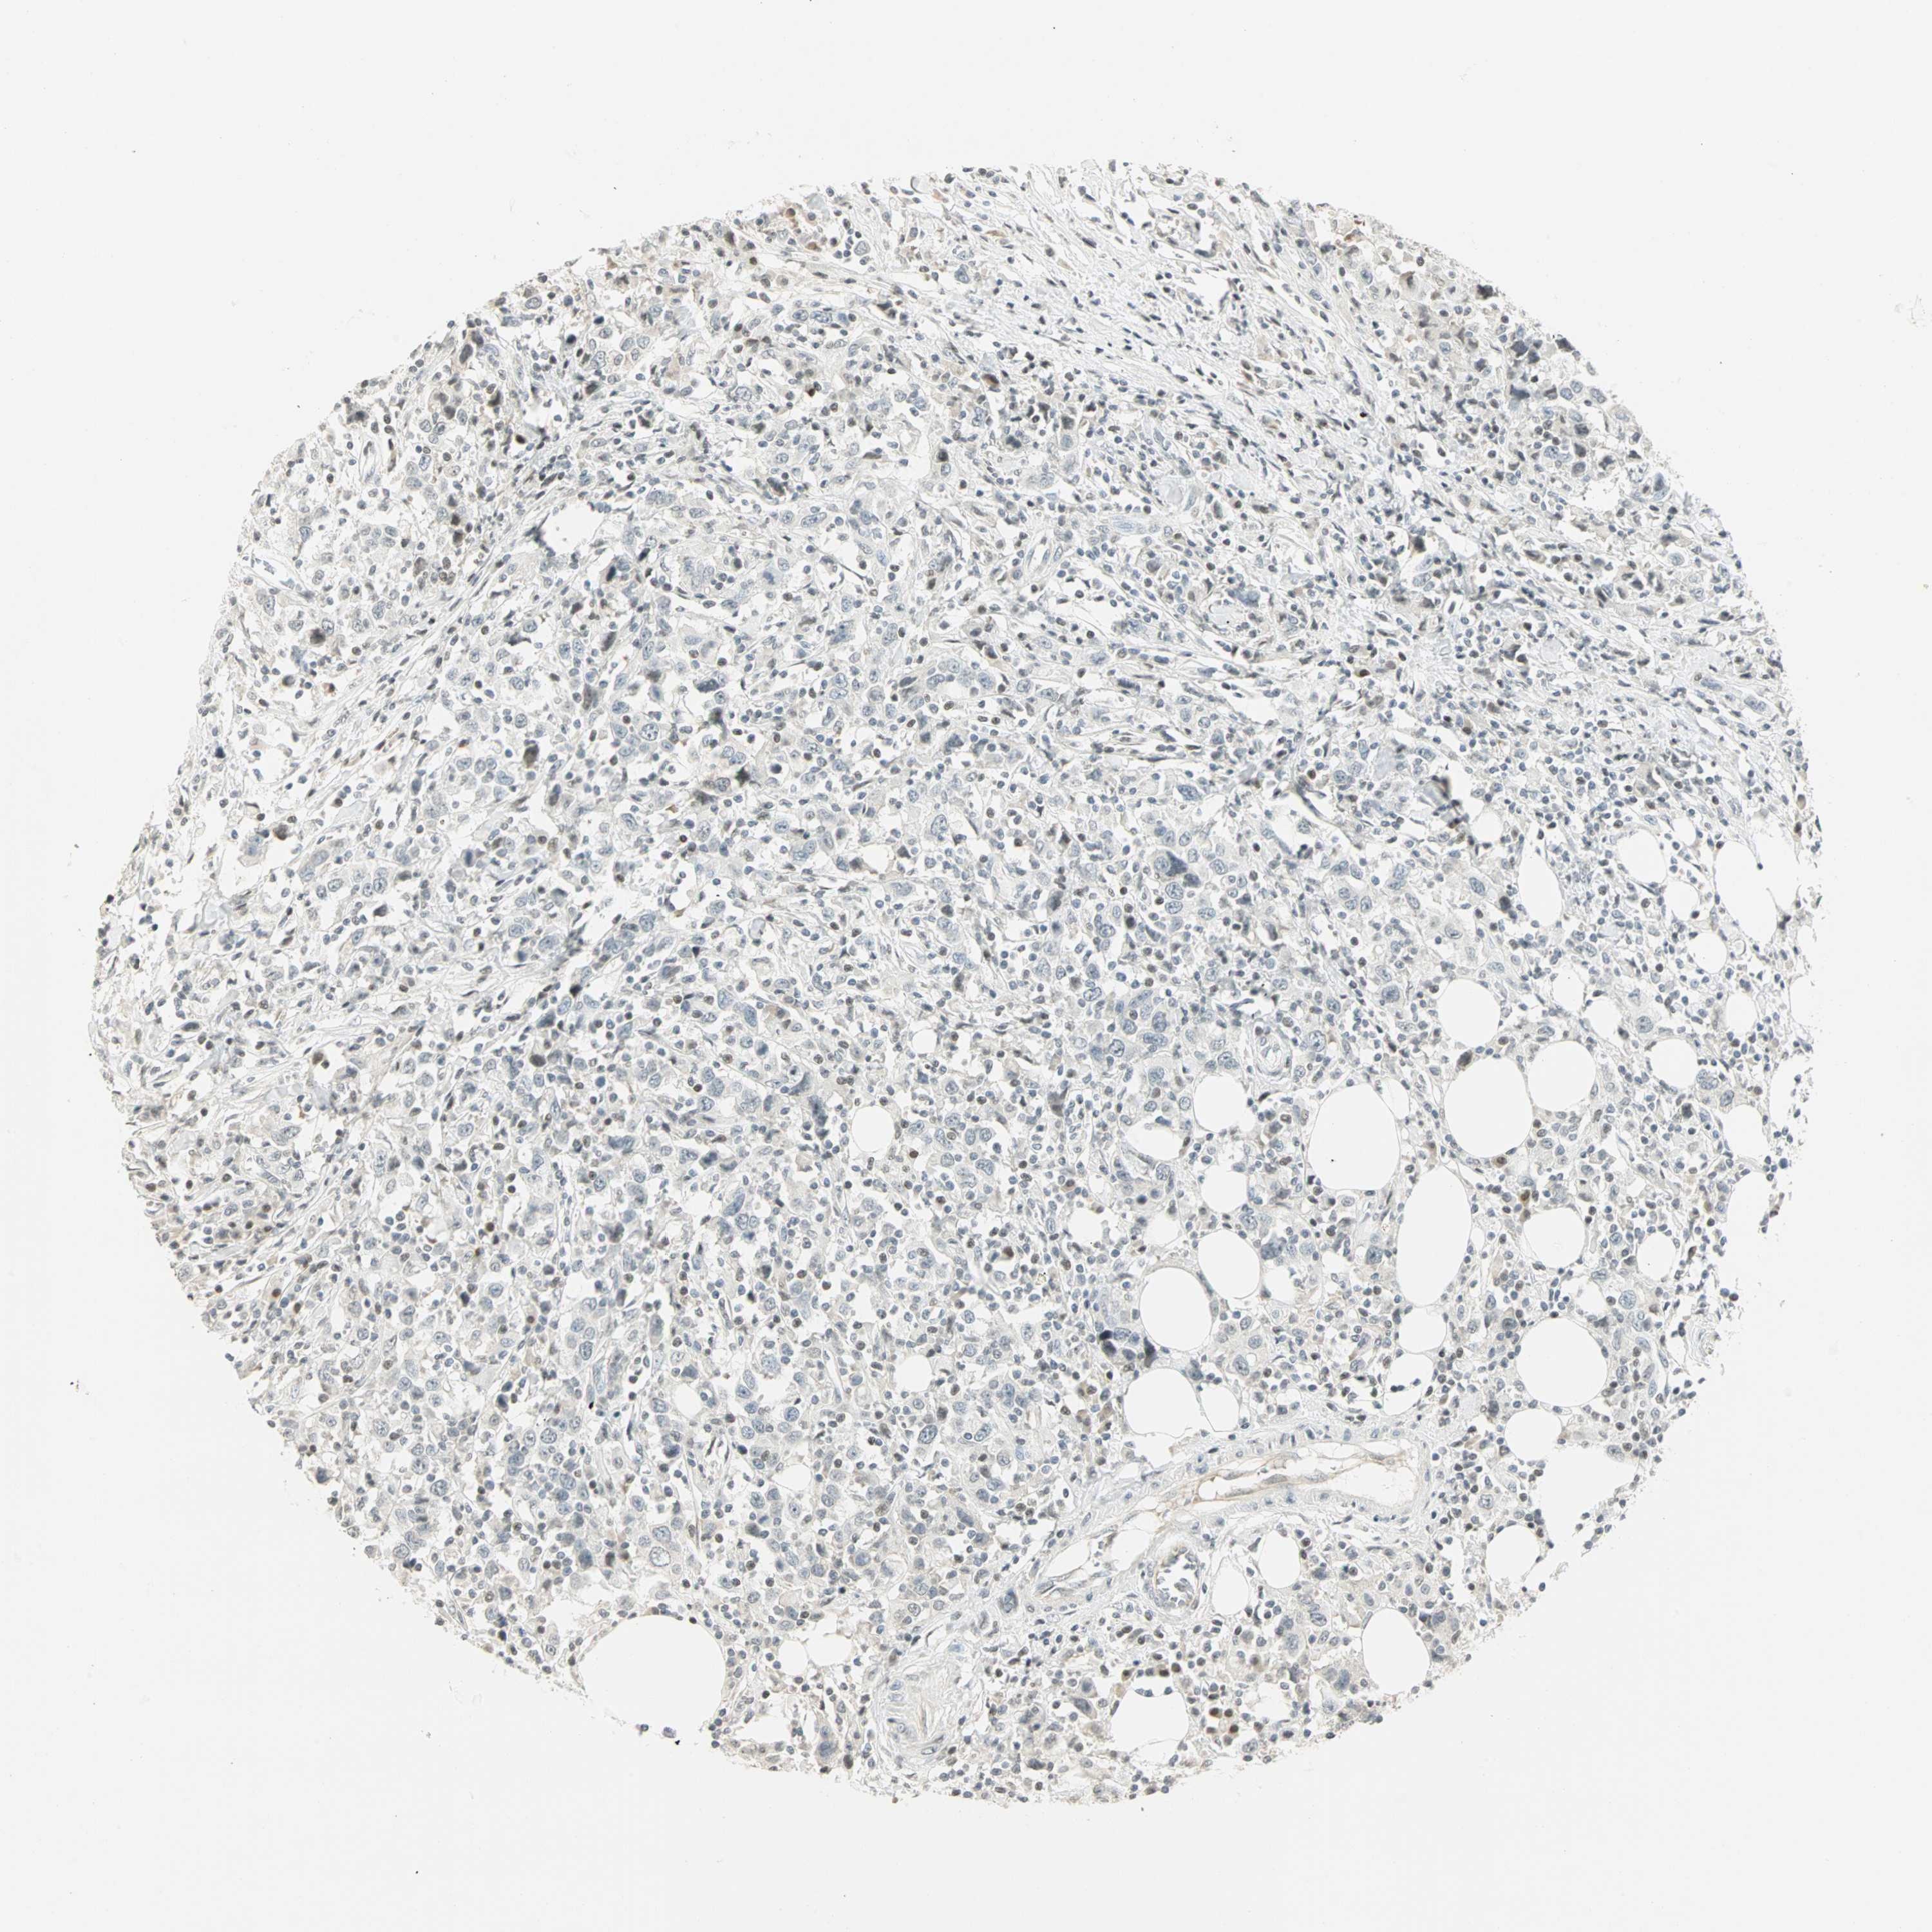

UROTHELIAL CANCER - Protein expressioni

A mouse-over function shows sample information and annotation data. Click on an image to view it in a full screen mode. Samples can be filtered based on level of antibody staining by selecting one or several of the following categories: high, medium, low and not detected. The assay and annotation is described here.

Note that samples used for immunohistochemistry by the Human Protein Atlas do not correspond to samples in the TCGA dataset.

Antibody stainingi

Antibody staining in the annotated cell types in the current human tissue is reported as not detected, low, medium, or high, based on conventional immunohistochemistry profiling in selected tissues. This score is based on the combination of the staining intensity and fraction of stained cells.

Each image is clickable and will lead to virtual microscopy that enables deeper exploration of all samples and also displays staining intensity scores, fraction scores and subcellular localization as well as patient and tissue information for each sample.

Antibody HPA067203

Antibody CAB008094

Antibody CAB069409

Staining

High

Medium

Low

Not detected

Intensity

Strong

Moderate

Weak

Negative

Quantity

>75%

75%-25%

<25%

None

Location

Nuclear

Cytoplasmic/membranous

Cytoplasmic/membranous,nuclear

Urothelial carcinoma, High grade

Urothelial carcinoma, NOS

Urothelial carcinoma, Low grade